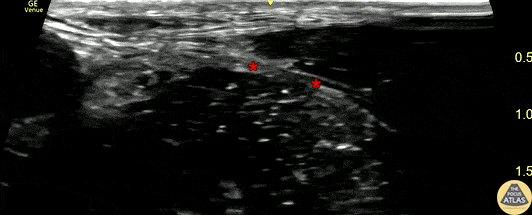

Teenaged male presented with a single GSW to the medial thigh. The trauma evaluation revealed a displaced and shortened transverse femur fracture. To facilitate traction pin placement and provide analgesia, a fascia iliaca block was performed. The block is shown here, with the needle is seen entering from the lateral aspect and depositing local anesthetic just deep to the fascia iliaca (*), lateral to the pulsating femoral artery. The patient had improvement of his pain and was able to be admitted to the surgical floor for operative repair the next morning. Dr. Phillip Breslow, PGY3 Denver Health Residency in Emergency Medicine